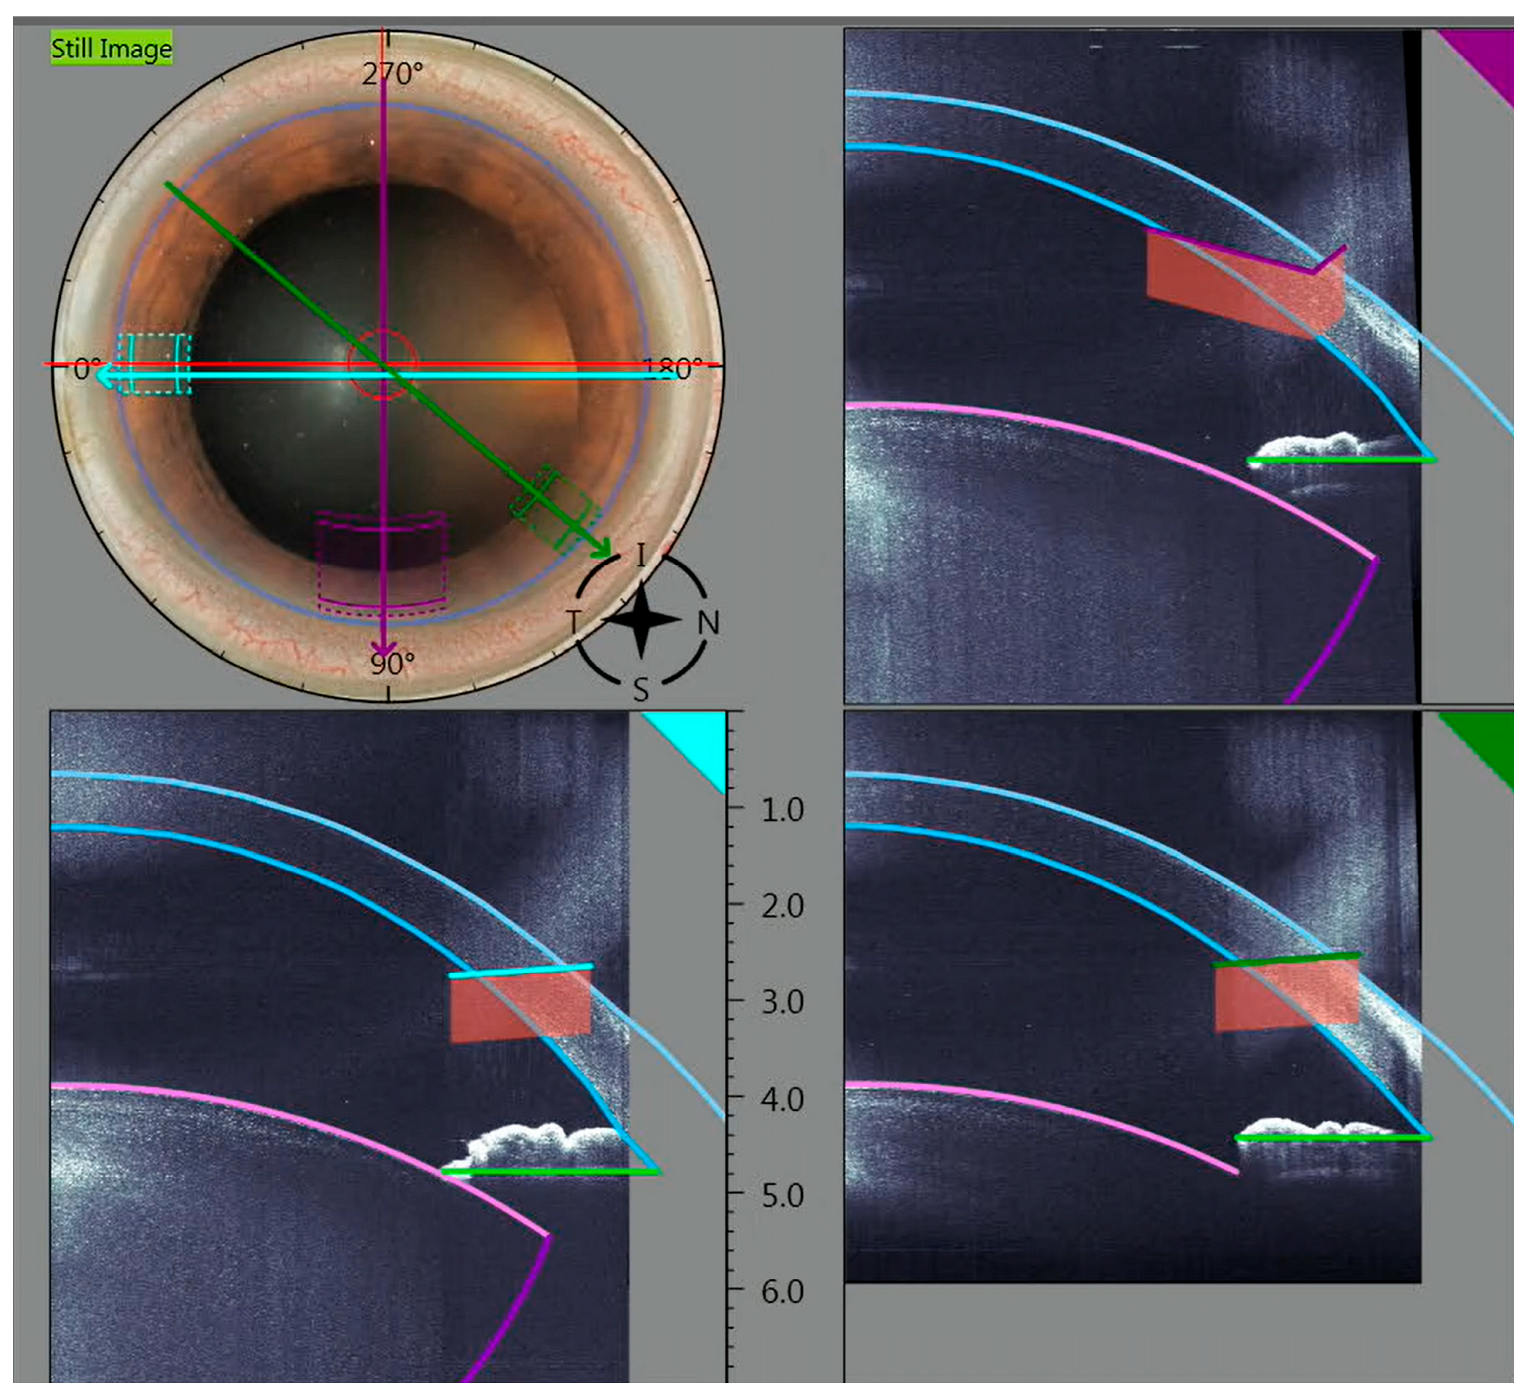

2.1. Surgical Technique